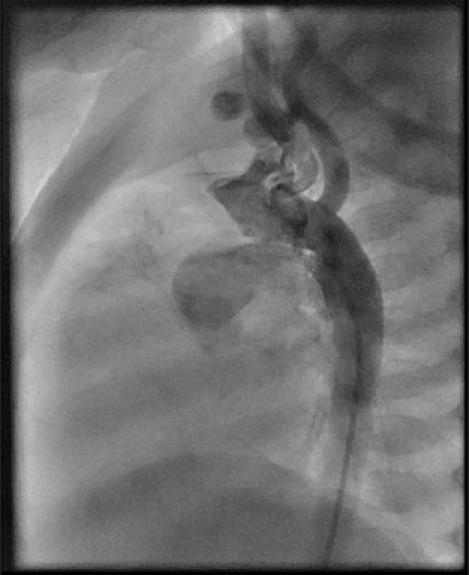

Five of six children aged 3-6 months with TGA-IVS and regressed LV underwent recanalization and transcatheter stenting of ductus arteriosus. The ductal stent was removed during arterial switch surgery.

The procedure was successful in 5/6 patients. All the patients had totally occluded ductus and needed recanalization with coronary total occlusion hardware. The ductus was dilated and stented with coronary stents. In all the patients, there was significant luminal narrowing despite adequate stent placement and deployment. Two patients needed reintervention for abrupt closure of the stent. Ductal stenting resulted in left ventricular preparedness within 7-14 days. One patient died of progressive sepsis after 14 days of stenting, even though the LV was prepared. Four patients underwent successful uneventful arterial switch surgery. During surgery, it was observed that the mucosal folds of duct were protruding through the struts of the stent in one patient.

该手术在5/6的患者中成功。所有患者的动脉导管均完全闭塞,需要使用冠状动脉完全闭塞器械进行再通。动脉导管用冠状动脉支架进行扩张和支架置入。在所有患者中,尽管支架放置和展开充分,但仍存在明显的管腔狭窄。2例患者需要再次干预以处理支架突然闭塞的情况。导管支架置入术在7至14天内使左心室得到准备。1例患者在支架置入14天后死于进行性脓毒症,尽管左心室已做好准备。4例患者成功进行了顺利的动脉Switch手术。手术期间,观察到1例患者的动脉导管黏膜皱襞穿过支架支柱突出。